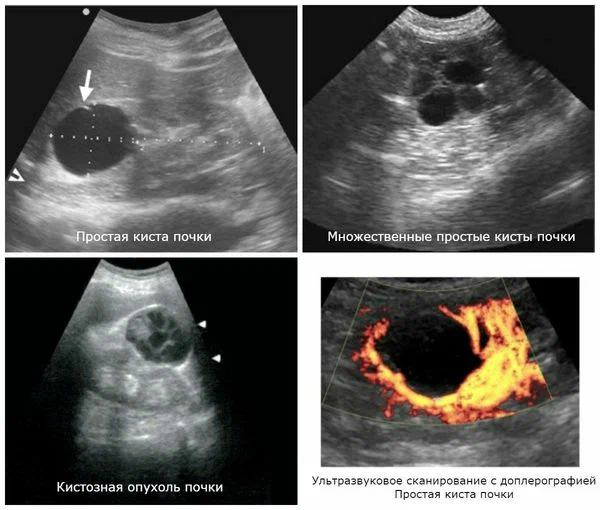

Итак, врач УЗИ пишет в заключении: «Киста почки»». Наиболее вероятно, это простая киста. Как раз такие и встречаются у 10% обследованных. Наилучший вариант из всех возможных, и вот почему.